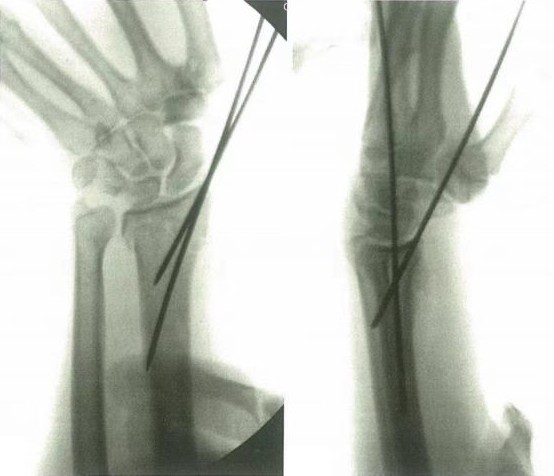

Zaprta redukcija, ki ji sledita perkutana pritrditev in fiksacija, je uporabna pri zlomih distalnega radiusa z metafizno nestabilnostjo ali preprostih intraartikularnih zlomih.

Prvi korak je anatomska repozicija, nato se izvede stabilizacija z gram zatiči. Običajno je prvi zatič prepeljan od radialnega stiloida do radialne metafize medialno do diafize.

Za zagotavljanje ustrezne stabilne repozicionacije v pravokotnem in bočnem položaju se uporabita najmanj 2 zatiča, po želji pa lahko lunatno faseto zapnete.

Intrafrakturna fiksacija (Kapanji tehnika) zagotavlja dorzalno oporo. Pooperativna imobilizacija v opornici se uporablja za 2 tedna za nadzor rotacije in zmanjšanje draženja zatiča, nato pa se lahko nadomesti z mehkim mavcem za podlaket.